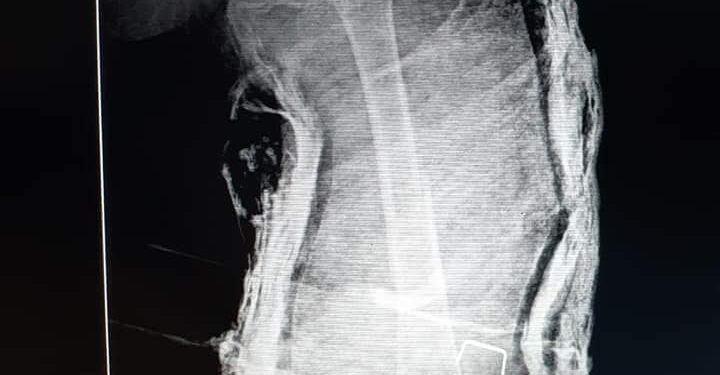

انه تم إجراء عملية رد كسر في عظمة الفخذ لطفلة عمرها ٣ سنوات تعاني من سرطان في الدم.

واضاف أبو طالب انه تم عمل بنطلون جبس للطفلة تحت جهاز الأشعة مما جنّب الطفلة التعرض لمخاطر العملية الجراحية.